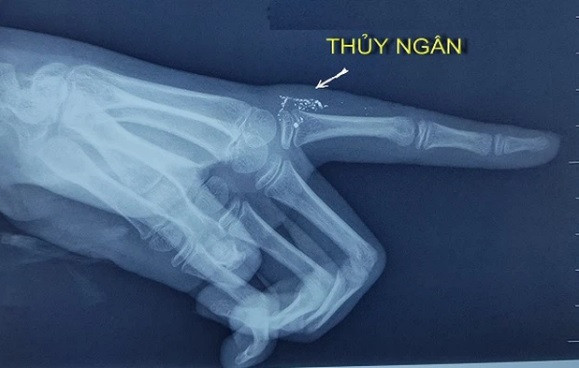

Những hạt thủy ngân trong tay qua hình ảnh phim X-quang. Ảnh: BVCC

Chiều 27/2, theo thông tin từ Bệnh viện Bạch Mai, hiện Khoa Nhi và Trung tâm Chống độc của Bệnh viện Bạch Mai đang điều trị cho một cháu bé bị nhiễm độc thủy ngân. Ngày 5/2, khi đang vẩy nhiệt kế thủy ngân để cặp nhiệt độ cho bé gái N.N.Y. (11 tuổi, ở Thái Bình), người nhà sơ ý khiến nhiệt kế chọc mạnh vào tay trái của cháu. Hậu quả, chiếc nhiệt kế bị vỡ gây ra vết thương ở ngón trỏ tay trái của Y. Khi nhập viện vào ngày 11/2/2021 (ngày 30 Tết), vết thương của Y. bị nhiễm trùng và áp xe. Kết quả chụp X-quang cho thấy, có nhiều hạt thủy ngân ở bên trong phần mềm sát khớp bàn ngón trỏ tay trái. Bác sĩ cho biết, đây là trường hợp đầu tiên nhiễm độc thủy ngân xảy ra do tai nạn khi sử dụng.